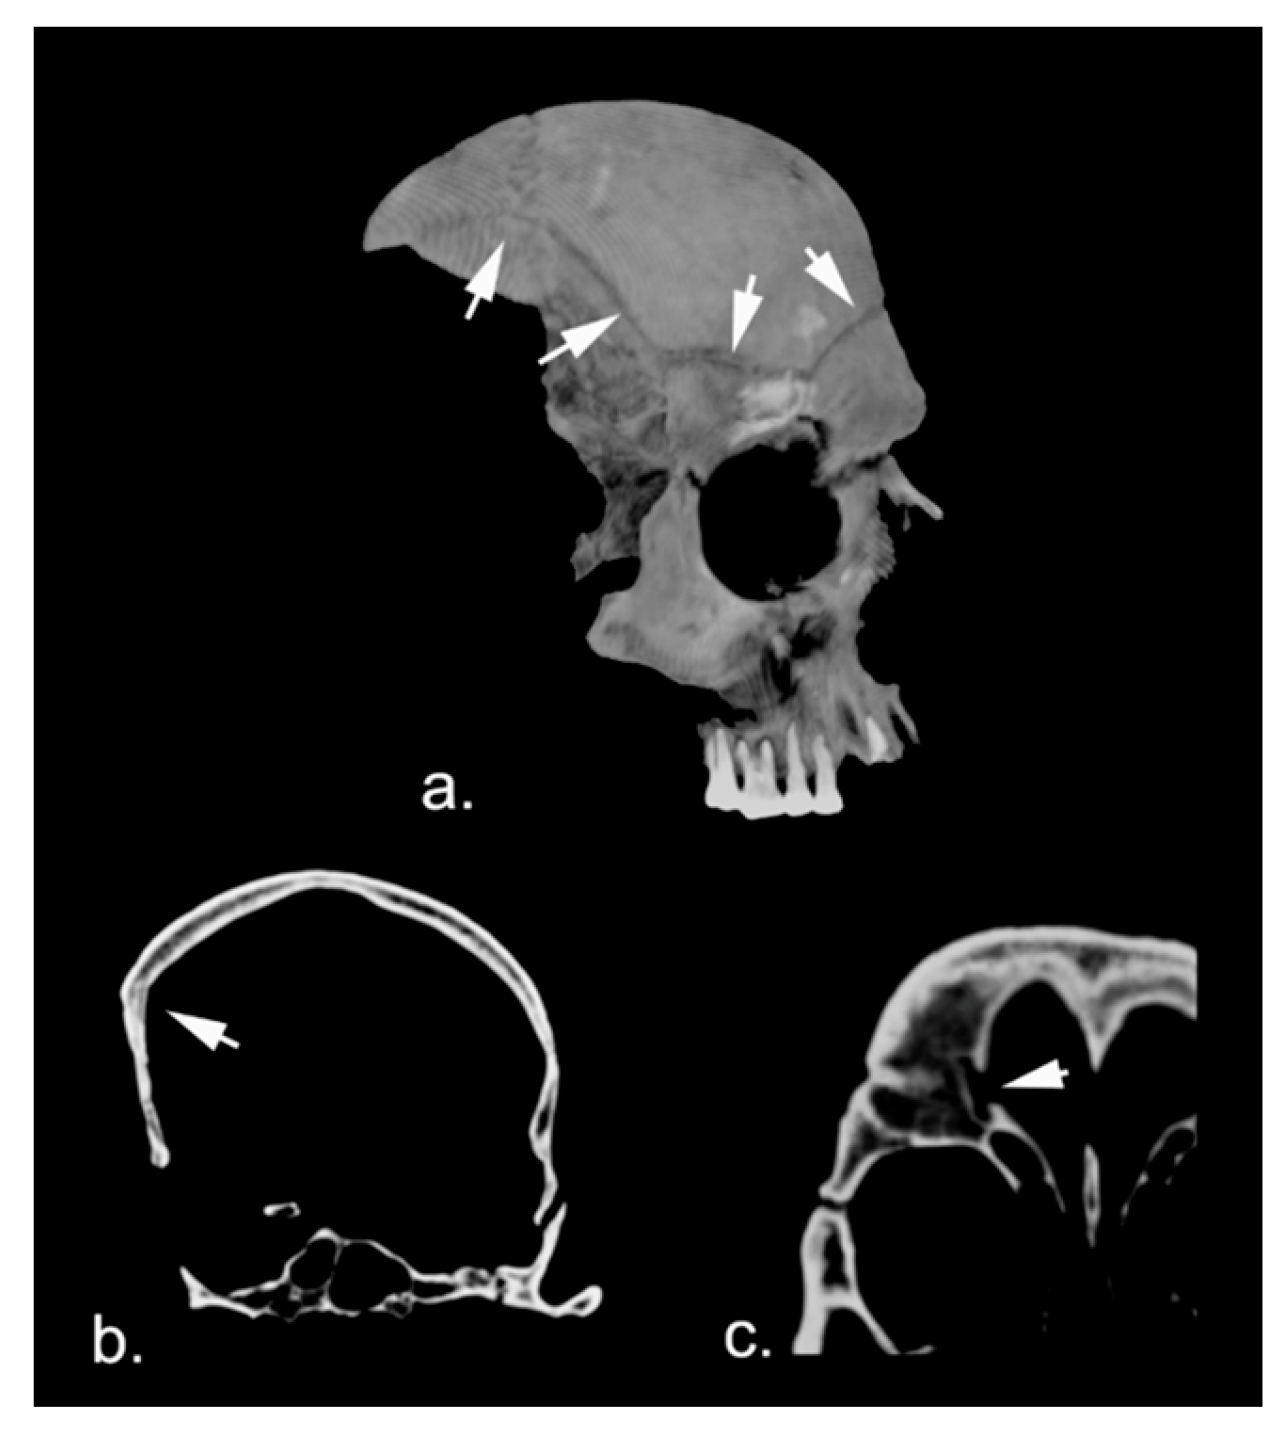

3.1. Anthropological and Radiographic Analysis